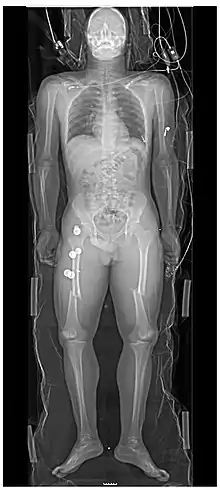

Les personnes ayant subi un traumatisme majeur ont souvent des radiographies du thorax et du bassin[22] et, selon le mécanisme de la blessure et la présentation, une évaluation ciblée avec échographie à la recherche d'hémorragie interne (FAST écho : focused assessment with sonography for trauma). Pour ceux qui ont une pression artérielle, une fréquence cardiaque et une saturation en oxygène relativement stables, les tomodensitogrammes sont utiles. Les tomodensitogrammes du corps entier, appelés body-scan, améliorent le taux de survie de ceux qui ont subi un traumatisme majeu[23],[24]. Ces scanners du corps entier (ou body-scan) utilisent des injections intraveineuses par produit de contraste (agent radioactif)[25]. On craint que l'administration de produit de contraste intraveineux dans des situations de traumatisme sans confirmation d'une fonction rénale adéquate puisse endommager les reins, mais cela ne semble pas être significatif[26].

Aux États-Unis, la tomodensitométrie ou l'IRM sont effectuées sur 15% des personnes ayant subi un traumatisme dans les services d'urgence[27]. Lorsque la pression artérielle est basse ou que la fréquence cardiaque augmente — probablement à cause d'un saignement dans l'abdomen — une intervention chirurgicale immédiate en contournant un scanner est recommandée[28]. Les tomodensitogrammes modernes à 64 coupes peuvent exclure, avec un haut degré de précision, des blessures importantes au cou après un traumatisme contondant[29].